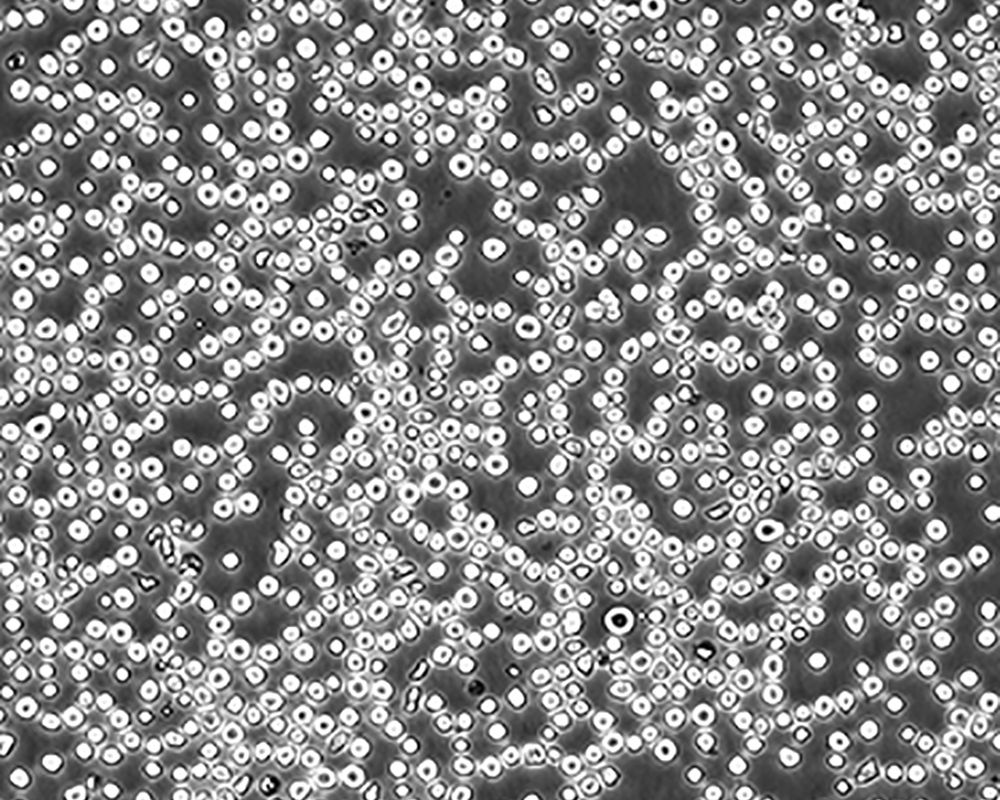

生長(zhǎng)特性 suspension

形態(tài)特征 lymphoblast

細(xì)胞描述 CEM/C1是人T細(xì)胞白血病細(xì)胞株CCRF-CEM(見(jiàn)ATCC CCL-119)具有喜樹(shù)堿抗性的衍生株。1991年細(xì)胞株選擇并亞克隆了對(duì)CPT的抗性。細(xì)胞表現(xiàn)出對(duì)CPT類似物水溶性的托泊替康和非水溶性的9-氨基-CPT及10,11-亞甲二氧基-CPT具有交叉抗性。CEM/C1細(xì)胞對(duì)CPT的敏感性較母系CEM細(xì)胞低31倍。CEM/C1細(xì)胞表現(xiàn)非典型的多藥抗性和轉(zhuǎn)換拓補(bǔ)異構(gòu)酶I催化活性。對(duì)CPT的抗性維持6個(gè)月以上。